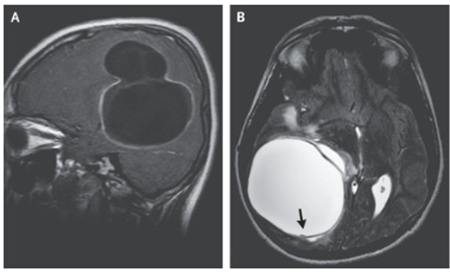

頭部MRI施行。T1強調像では右側頭頂部領域に60×62×58mmの多房性膿疱を認め、T2強調像では低信号の縁と小突起(矢印↓参照)を認めた。

(A:T1強調像、Sagittal)(B:T2強調、axial)